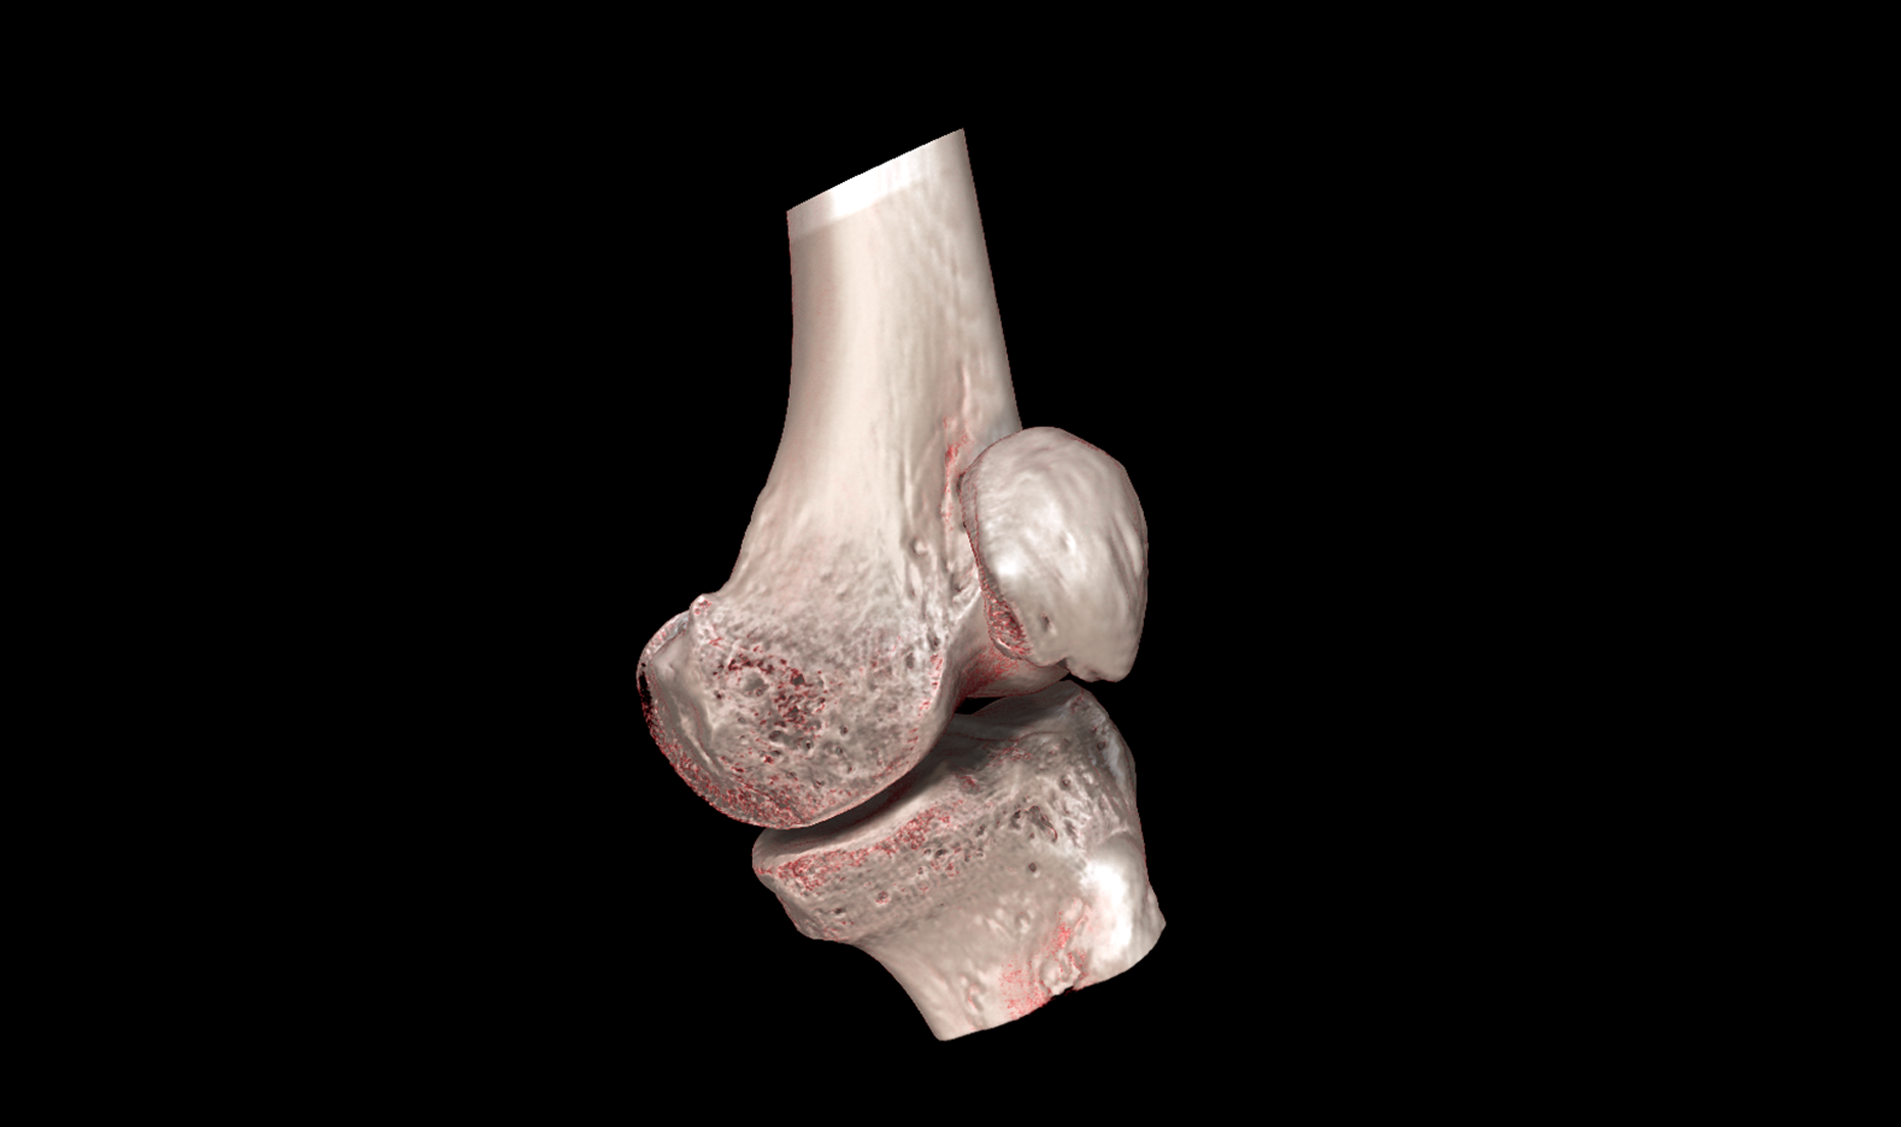

HDVI and HRCT

SPATIAL RESOLUTION

Outstanding image quality in hard tissues.

NON INTERPOLATED 3D DATA VOLUME REPRESENTATION

Acquisition of volumes with 100% real data: perfect for augmented reality, orthopedics and image-guided procedures.

Human CT Scanner Innovation

Imaginalis innovative vision has led to a new milestone: the development of a human CT scanner that promises to revolutionize the medical sector, particularly in orthopedic applications.

Precision Diagnosis & Treatment

Our scanner introduces advanced technology that offers high-resolution images and greater imaging flexibility, allowing for more precise diagnosis and optimized treatment planning.